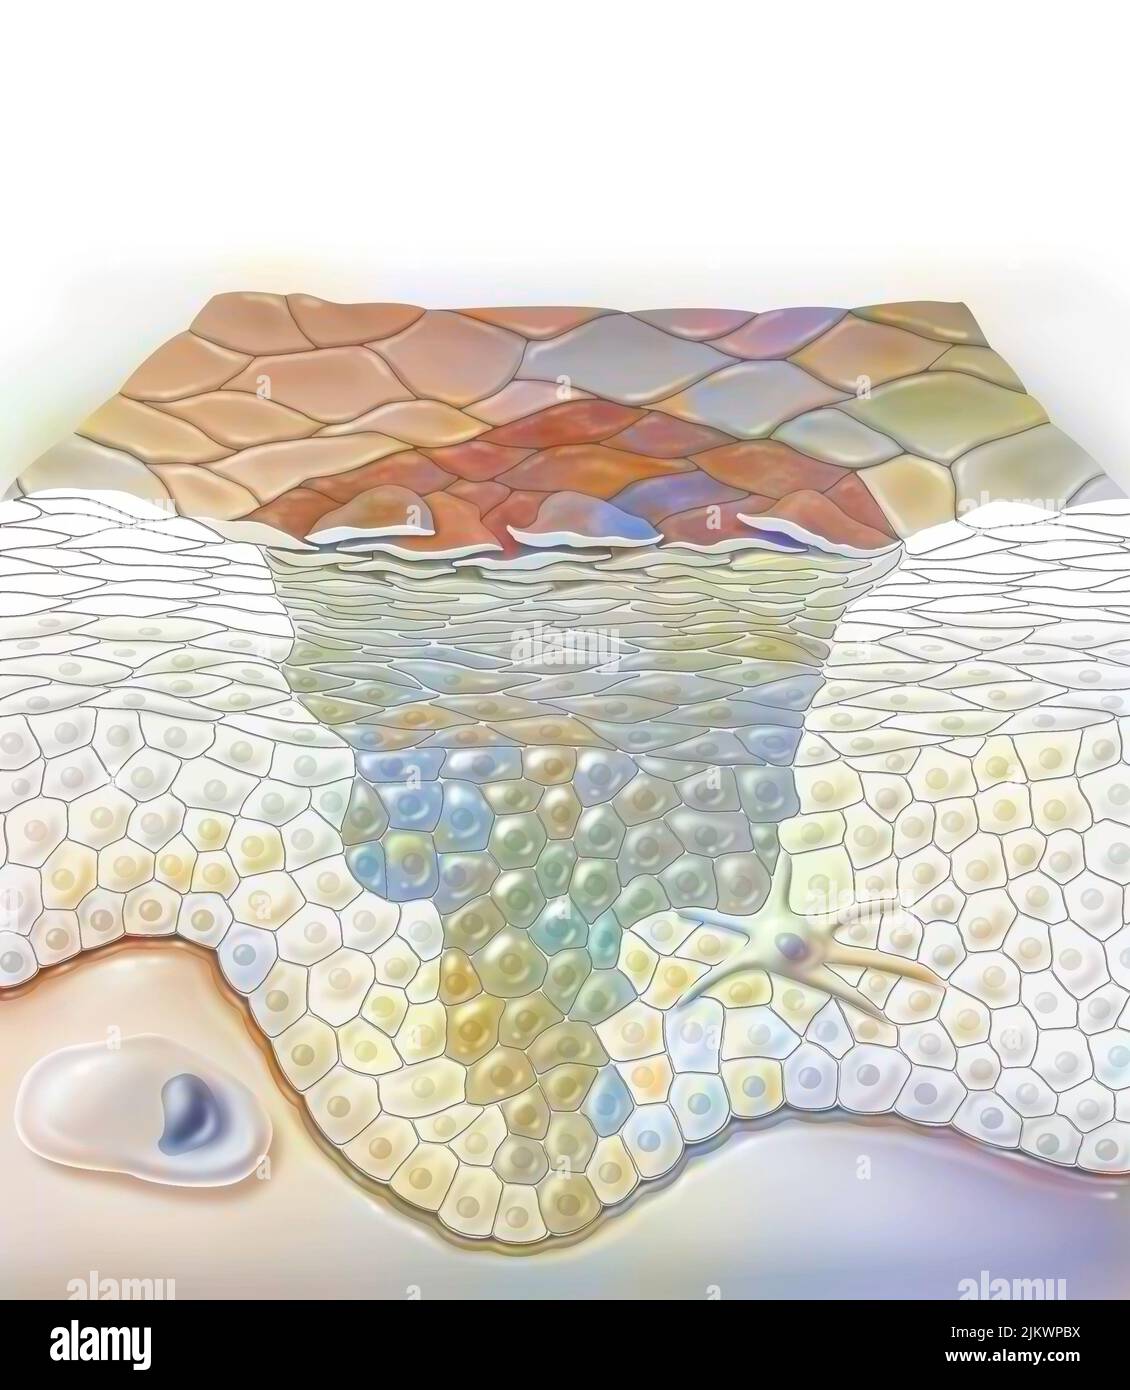

RF2JKWPGK–Acide aminé non synthétisé par la voie du ribosome dont seul l'acide de gauche peut être synthétisé par les ribosomes. C'est pourquoi la synthèse des antibiotiques est si complexe.